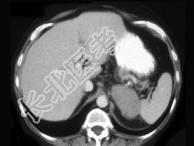

- 单项选择题女,47岁, 满月脸、向心性肥胖伴高血压1个月,请结合所提供图像, 作出诊断 ( )

A、左肾上腺腺瘤

B、左肾上腺腺癌

C、左肾上腺转移瘤

D、左肾上腺嗜铬细胞瘤

E、左肾上腺增生